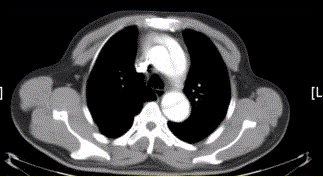

问题 患者男,67岁,高血压病史多年,自服降压药,突发胸骨后剧烈疼痛2h,服用硝酸甘油不缓解。胸透示主动脉增宽。CT影像如下图。 本例分型属

选项 A.DebakeyI型 B.DebakeyIIa型 C.DebakeyIIb型 D.DebakeyIII型 E.StanfordA型 F.StanfordB型

答案 AE